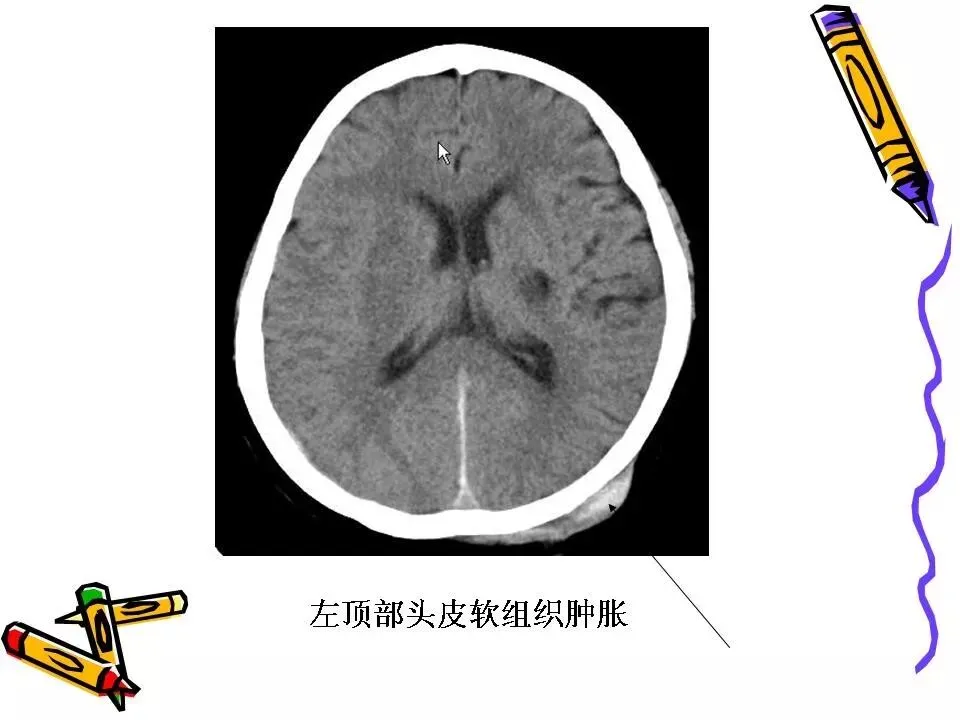

>常见颅脑外伤CT诊断(PPT)

常见颅脑外伤CT诊断(PPT)